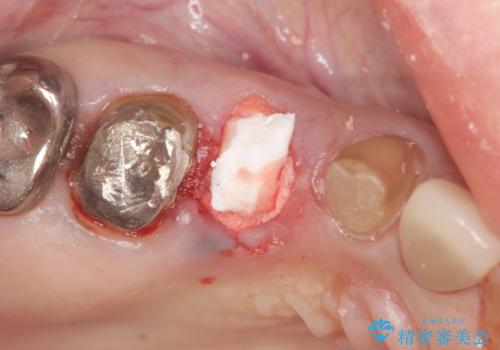

また単純に抜歯のみを行うと歯ぐきが大きく凹み、ブリッジの清掃性が損なわれることが予想されるため、抜歯時に歯槽堤保存術を行い

清掃性の高い仕上がりとなるよう配慮しています。